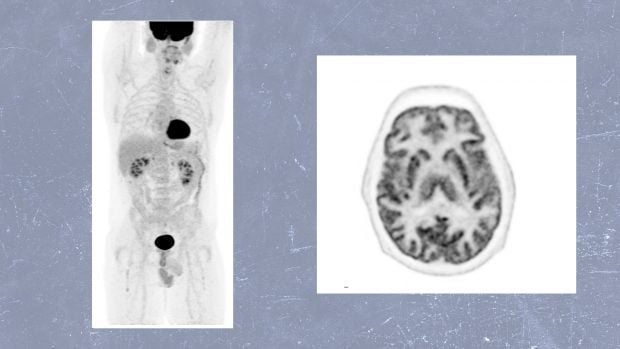

Bien, esa prueba médica a la que nos referimos existe, se aplica en el ámbito sanitario y se denomina Tomografía por Emisión de Positrones – Tomografía Computarizada (PET-TC). Se trata, en concreto, de una técnica poco invasiva, como veremos, que ofrece una gran información sobre el estado del organismo de los pacientes que se someten a ella. Esta combinación, denominada imagen híbrida, permite determinar el comportamiento de la enfermedad, especialmente maligna, y también localizar exactamente las lesiones patológicas.

Por un lado, la TC muestra la estructura o la anatomía. «Es decir, el tamaño de los órganos, la forma de los tejidos, la localización de posibles lesiones», señala. Mientras que la PET, aclara, «nos muestra cómo están funcionando esas zonas, indicándonos qué tejidos, células y ámbito molecular tienen más actividad o metabolismo». Ésto, según el Dr. Soriano, es «muy importante» porque «muchas enfermedades comienzan con esa alteración, antes incluso de que cambie la anatomía o que la estructura altere su comportamiento».

La PET-TC combinada con la sustancia 18-FDG, prosigue, se usa sobre todo en Oncología, ya que «permite detectar tumores, su extensión y/o propagación, evaluar tratamientos y detectar recaídas precozmente». Pero no sólo se usa en casos de cáncer, también se aplica en Cardiología, «ayudando a saber si una zona dañada del corazón todavía puede recuperarse (tejido viable)» o en Neurología, «al permitir estudiar focos de epilepsia o enfermedades neurodegenerativas, como enfermedad de Parkinson y demencias como el Alzheimer y otras causas».